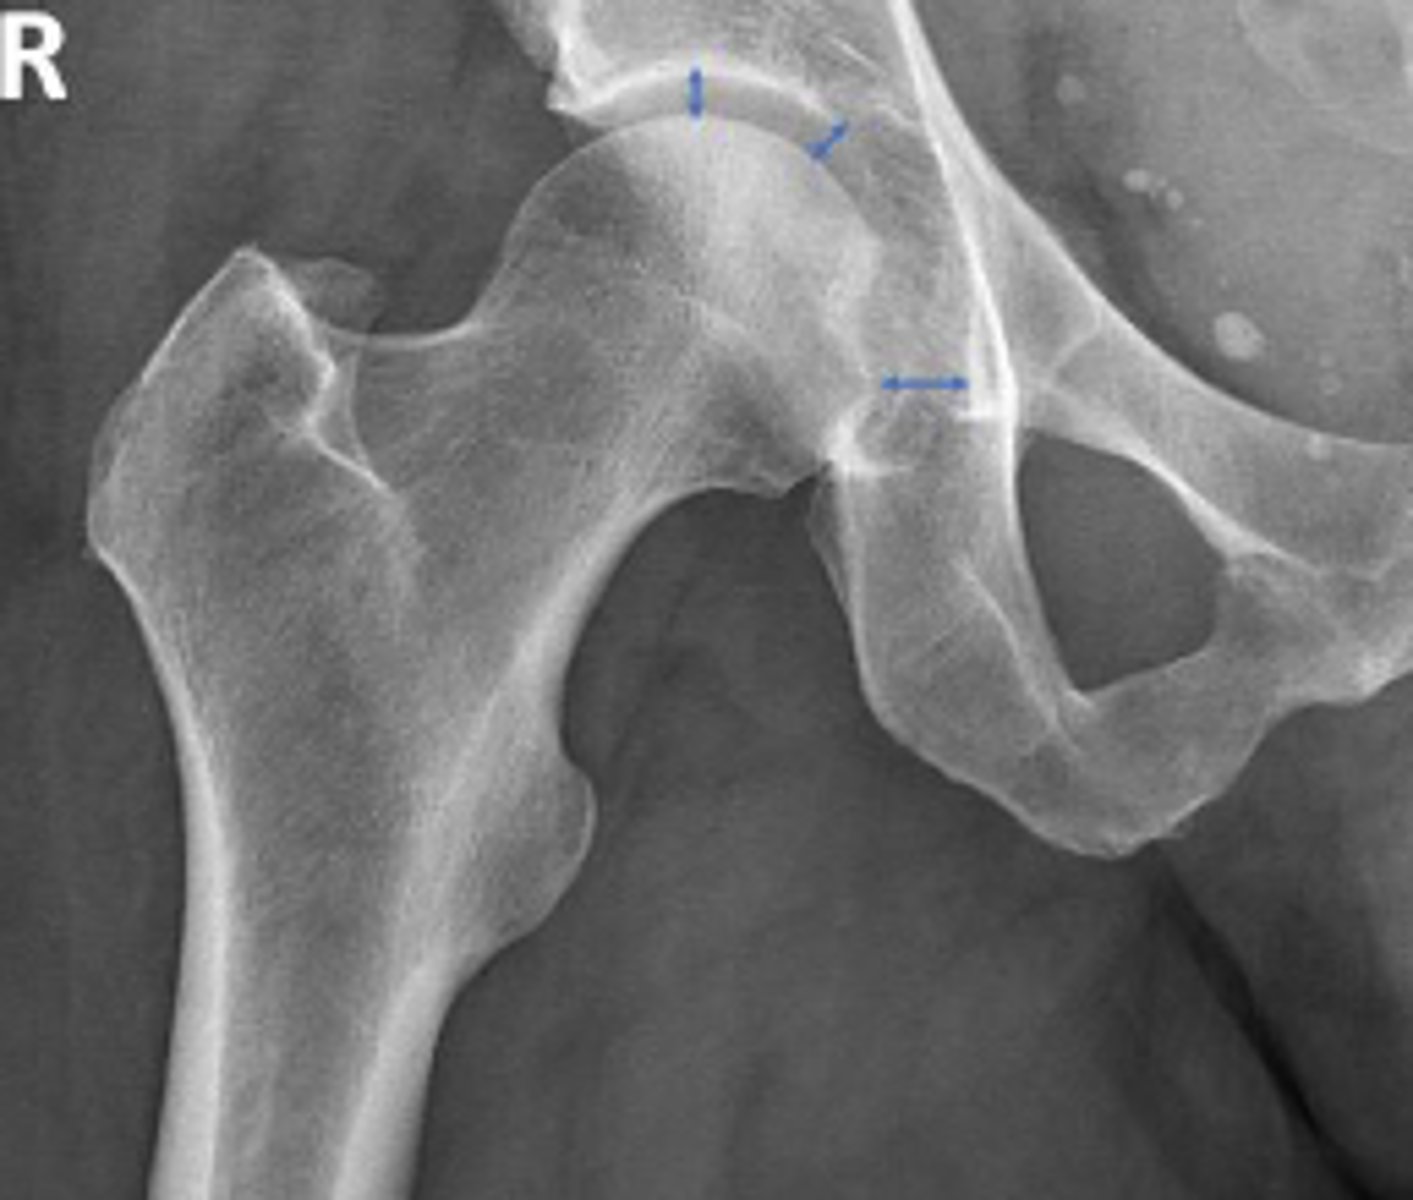

AP right hip

What is the radiographic view?

Teardrop distance

What is the name of the assessment?

6-11mm

What is the normal range for this assessment?

The distance between the most medial margin of

the femoral head and the adjacent pelvic

teardrop

What are the osseous landmarks for this assessment?

Yes (normal is 6-11mm)

Is the measurement within normal limits?

Femoroacetabular joint inflammation

Name 1 condition that may result in a measurement of 15mm?

AP pelvis and AP hip views

Name 2 radiographic views for this assessment?

Late stage degenerative joint disease

Protrusio acetabuli

Name 2 conditions that may result in a measurement of 3mm?

Waldenstrom's sign

What is the named sign if this assessment has a value > 2mm difference

between the left and right side?

Hip joint space width

Superior joint space is 3-6mm

Axial joint space is 3-7mm

Medial joint space is 4-13mm

Superior joint space-> The measurement between the most convex superior aspect of the femoral head and the adjacent acetabulum

Axial joint space -> The measurement between the

femoral head and the acetabulum lateral to the

acetabular notch

Medial Joint space -> The measurement between the most medial margin of the femoral head and the adjacent pelvic teardrop

Yes

Are the measurements within normal limits?

Degenerative joint disease

Name 1 condition that may result in a measurement of <3mm for the superior joint space?